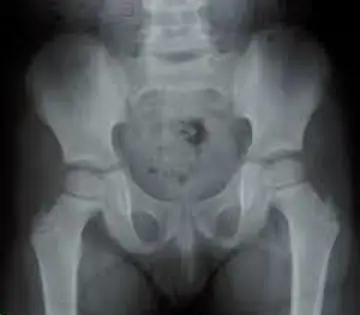

حساسیت رادیوگرافی درصدمه‌های لگن کودکان

شماره ۱۰۲۶